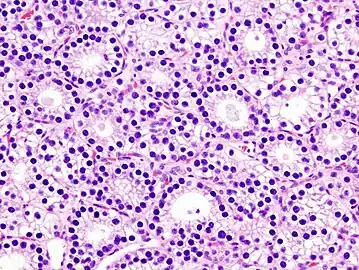

Histopatholgical image of parathyroid adenoma in a patient with primary hyperparathyroidism. Hematoxylin and eosin stain. -

Histopatholgical image of parathyroid adenoma in a patient with primary hyperparathyroidism. Hematoxylin and eosin stain. Another view of the same lesion